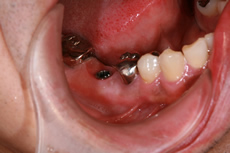

インプラント症例

術前